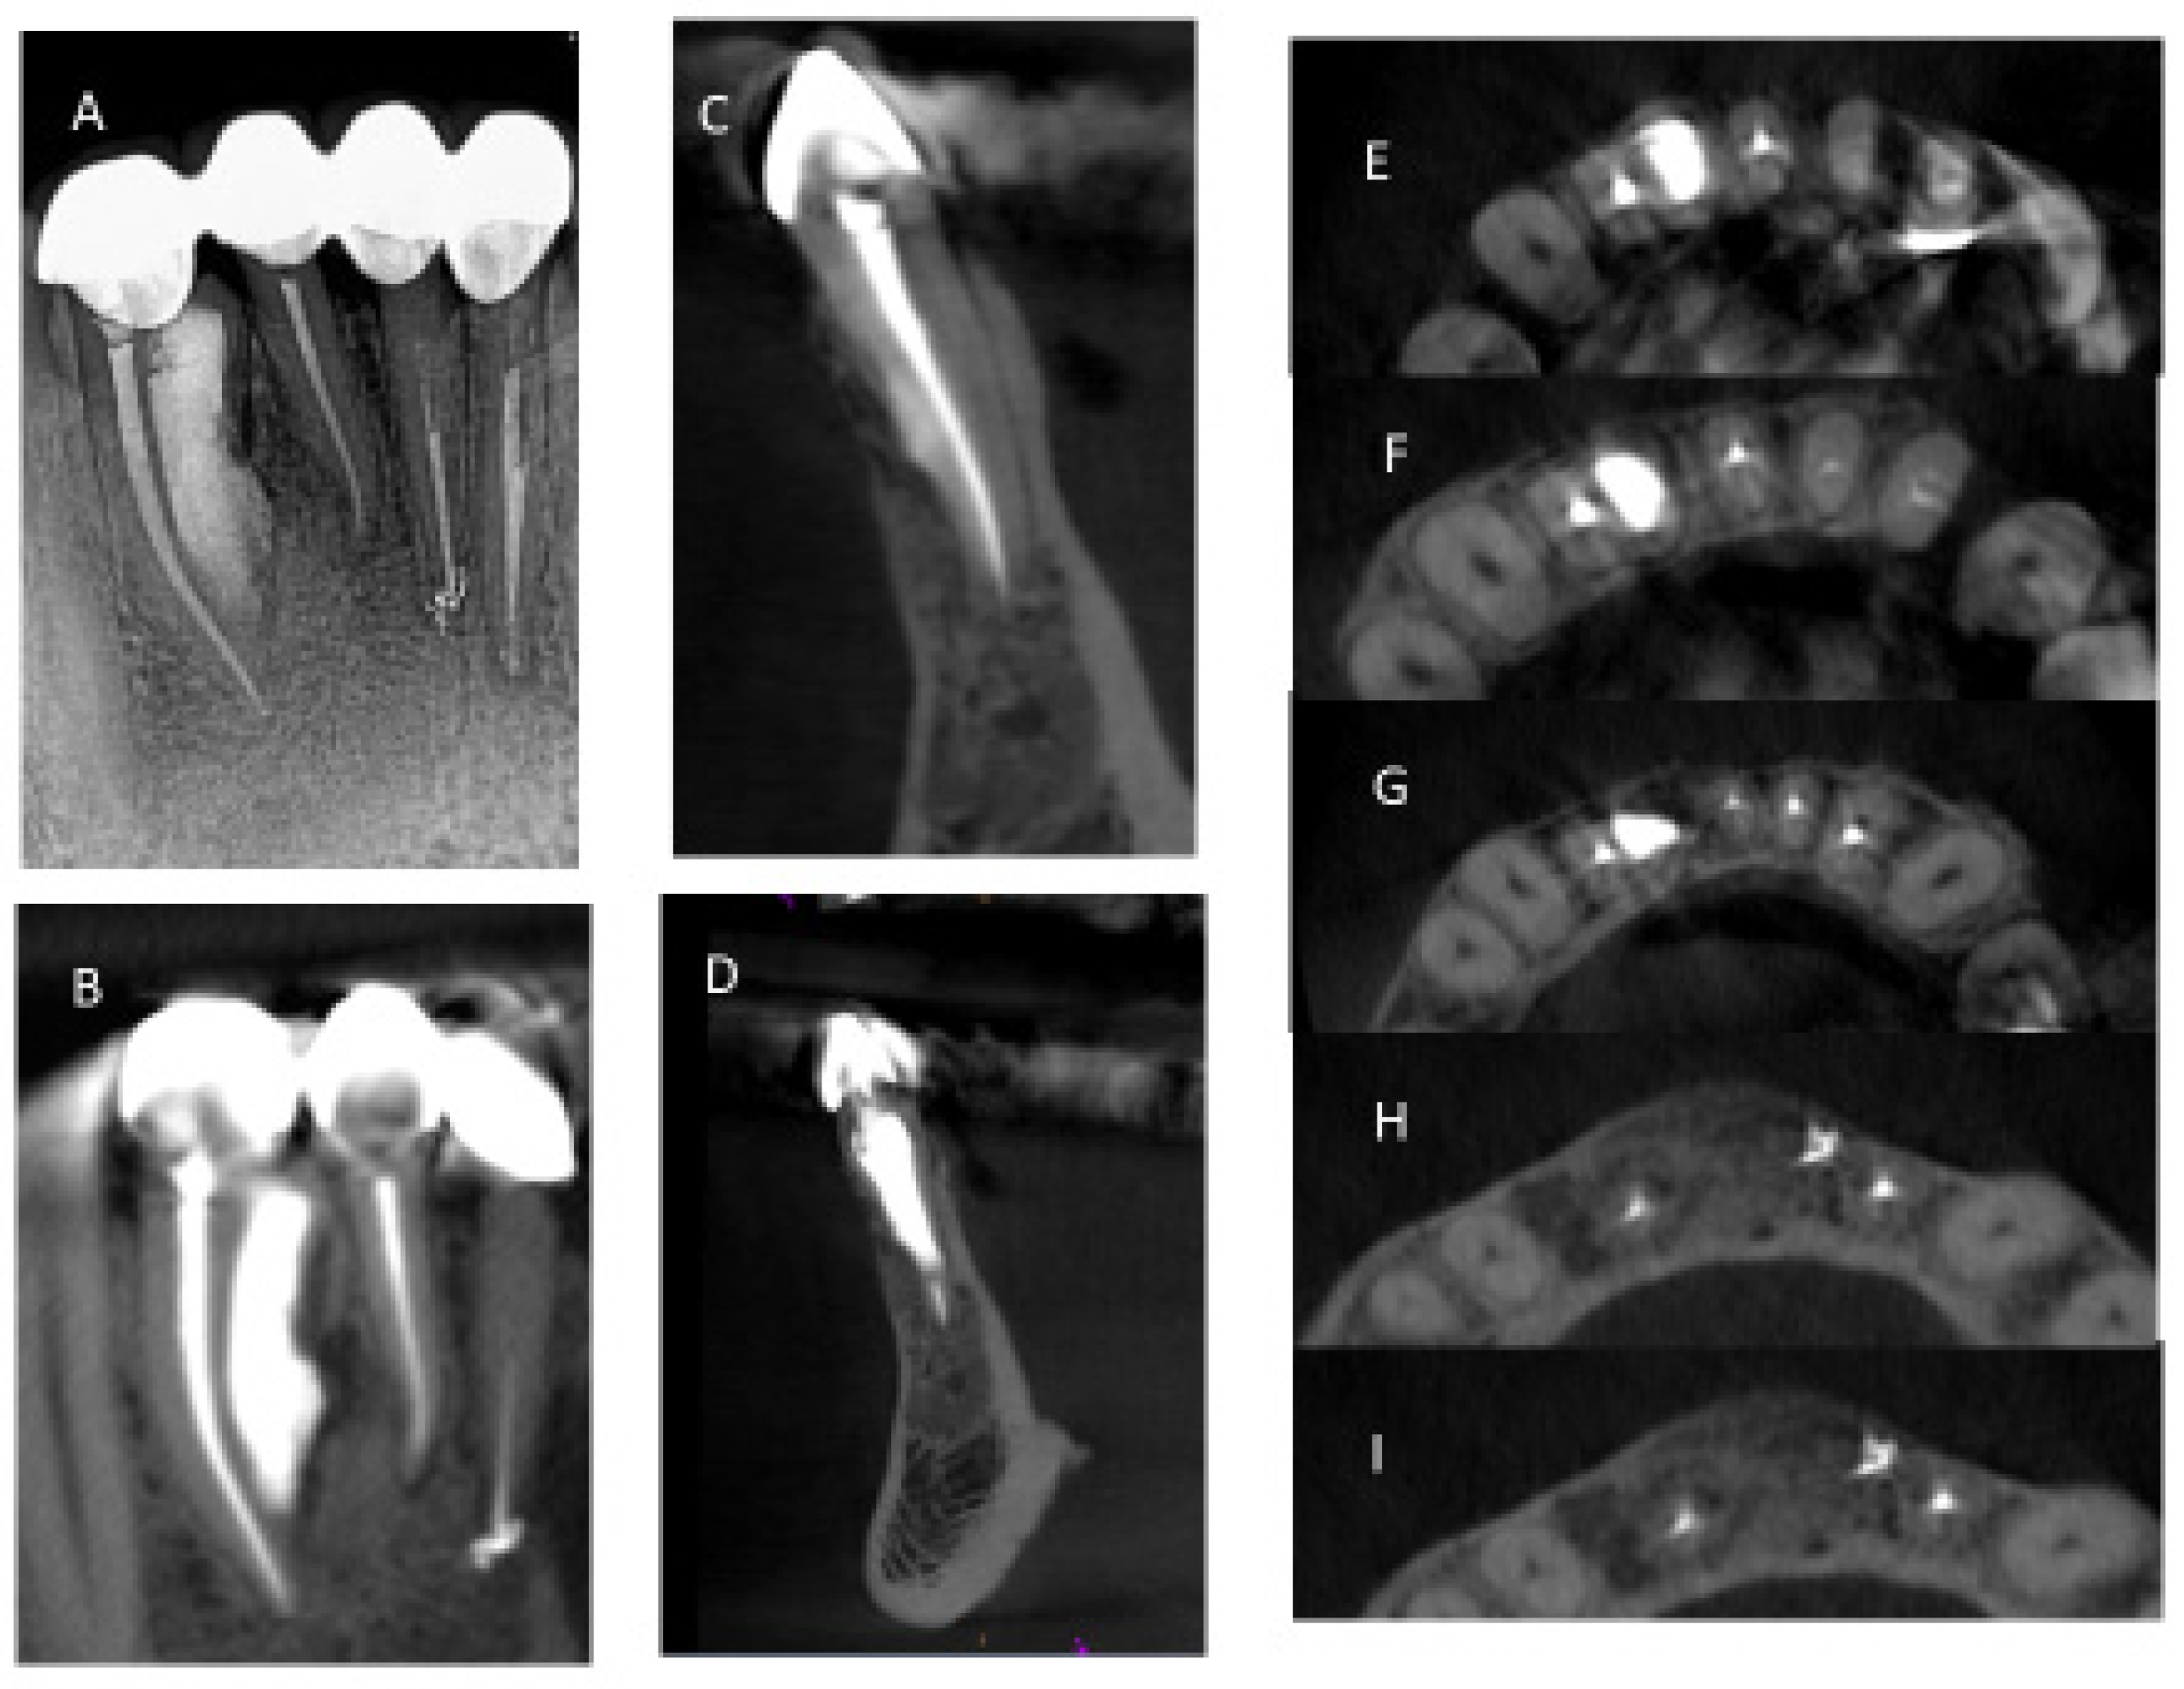

Figure 1. (A) Initial PA taken at endodontic evaluation of tooth #26. (B) Mesial and distal endodontic access cavities. (C) Pretreatment CBCT sagittal section. (D) Final PA after completion of nonsurgical and surgical endodontic treatments and restoration. (E) Photograph of restored tooth #26. (F) Post-treatment CBCT at 6-month follow-up.

Figure 9. Post-treatment CBCT at 36 month follow-up showed bony healing on 2D image (A) and on small FOV CBCT coronal section (B), sagittal section (C,D), and axial sections (EI).